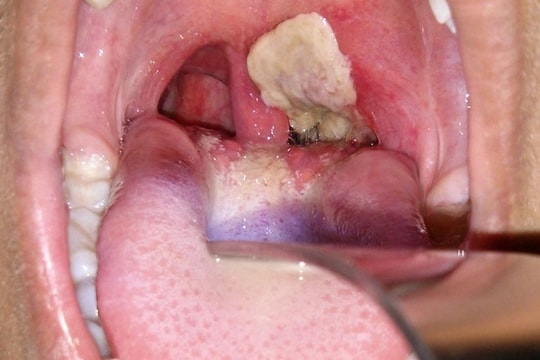

Bệnh bạch hầu, bạn cần biết - Kỳ 1: Nguyên nhân gây bệnh và lây nhiễm

Bệnh bạch hầu, bạn cần biết - Kỳ 2: Cách chữa trị bệnh bạch hầu

Bệnh bạch hầu, bạn cần biết - Kỳ 3: Thế giới đối phó với bệnh bạch hầu